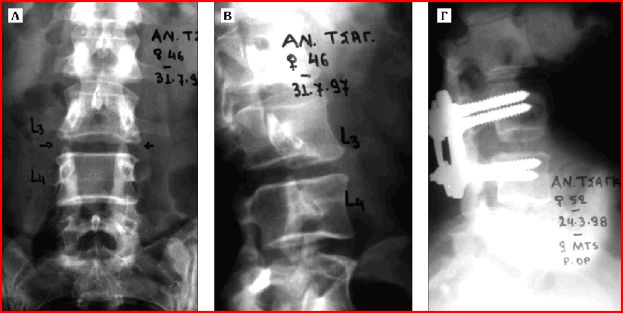

• Εκφυλίστικές παθήσεις (Spinal Degenerations)

• Disc – Δίσκος